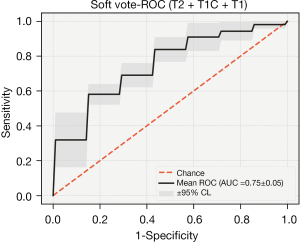

After combining the key features of the different sequences, the performance of the three sequences was greatly improved in the integrated classification model [ACC: 0.796 (0.76, 0.833), AUC: 0.689 (0.615, 0.763)]. The average accuracy rate was close to 80%, and the average AUC exceeded 70%. Furthermore, the performance was stable, and the accuracy rate was higher than 70% in multiple sequence combinations.

After the combination of features, the performance of the other models improved to varying degrees. The average accuracy of the RF was 0.771 (0.727, 0.816), and the AUC was 0.697 (0.614, 0.78).

After combining the key characteristics of the different sequences, the combined effect of the three sequences was greatly enhanced in the ensemble model [ACC: 0.796 (0.76, 0.833), AUC: 0.689 (0.615, 0.763)]. The average accuracy rate was close to 80%, and the average AUC exceeded 70% (Figures 9,10).

After analyzing the commonly used classifiers for brain tumors (25,26), we chose five models for classification: logistic regression (logistic), RF, KNN, SVM, and a soft voting integrated model (RF, SVM). The integrated classification model based on RF and SVM had the best predictive performance, which could be due to the combination of the advantages of the two models. In our research, T2W had the highest performance in predicting the expression level of Ki-67 in all sequences, and the acquired image features had a unique degree. The accuracy of the T1W sequence was slightly worse than that of the T2W sequence. In addition, we did not just identify a single sequence to predict the patient’s Ki-67, but also performed seven combinations of three sets of sequences.

In this study, based on the image features of the three sequences of T1W, T2W, and T1WC, three feature selection methods were used to construct the prediction model, which had good accuracy in predicting the expression of the Ki-67 index. Clinically, the proposed tool has important guiding significance for analysis and judging the growth, differentiation, and prognosis of MB.